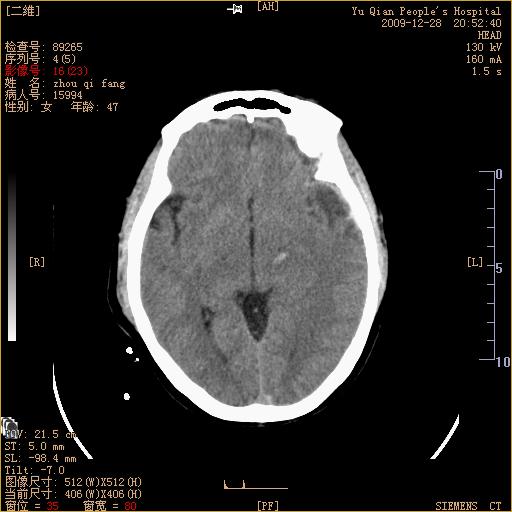

头部外伤后1天   请看看左侧丘脑外侧原是否为小血肿?(两天表现大致相仿。)谢谢

左颞叶前外部见片状挫裂伤,左丘脑小血肿;颅板下见多发小片状血肿影,两侧额部见少量蛛网膜下腔出血,

左额叶颅内板下也有一高密度灶。。。考虑多发小灶性出血(挫裂伤)。。。复查后再定

不好定。同时左侧裂池形态异常,左侧豆状核点状高密度,第四幅右额叶稍高密度影,最后一幅左额叶颅骨内板下方小片状高密度影。复查。